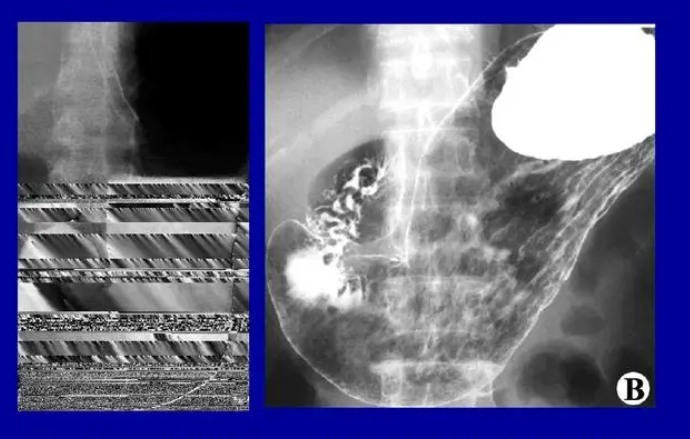

5. Medical imaging:

Barium metal has important applications in medical imaging. Barium is a commonly used contrast agent for gastrointestinal X-ray examination. Barium agents can make the gastrointestinal tract display clearer, which helps doctors diagnose and treat diseases. In addition, barium metal can also be used for medical examinations such as bone density measurement.